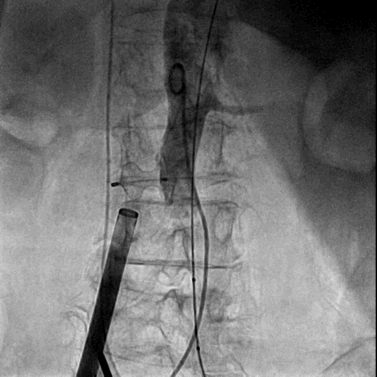

完成瓣膜置入后撤出22F输送鞘并用封堵器封堵腹主动脉与下腔静脉间的动静脉瘘,封堵器完全释放后腹主动脉及下腔静脉内造影均显示封堵效果良好,未见明显造影剂外渗。

封堵器释放后腹主动脉造影

封堵器释放后下腔静脉造影